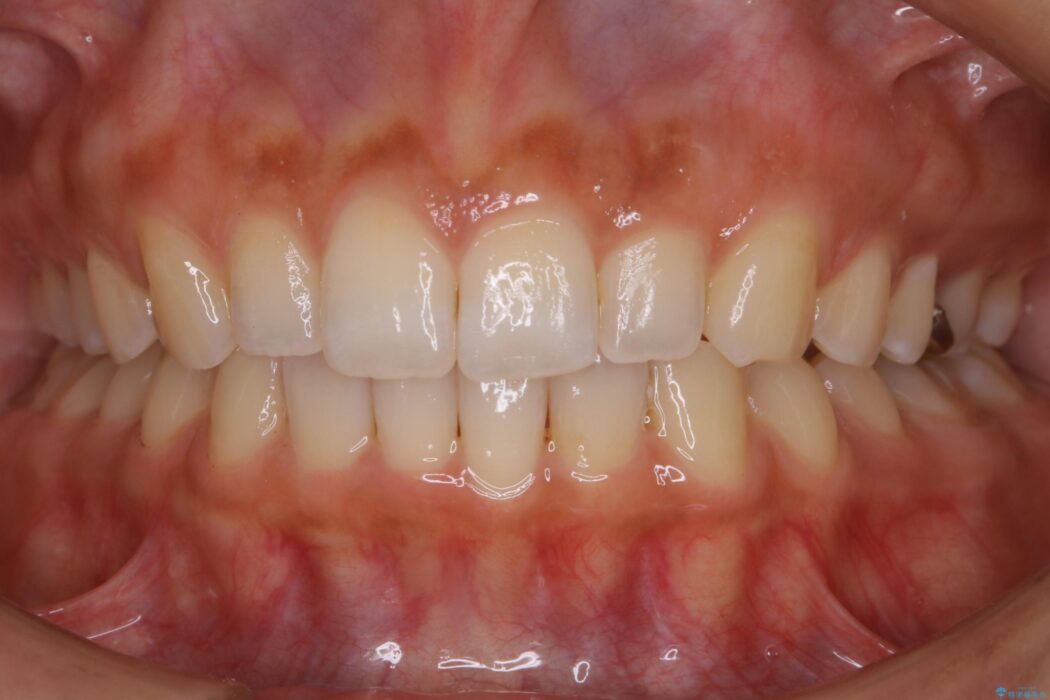

気になるガタツキと噛み合わせを改善したいとご来院されました。

下の歯列よりも上の歯列が前に出ている状態を治すため、マウスピース矯正に加え、患者様にゴムかけのご協力をいただきました。その結果、ガタつきが改善し、上下の噛み合わせが適切な位置で合うようになりました。